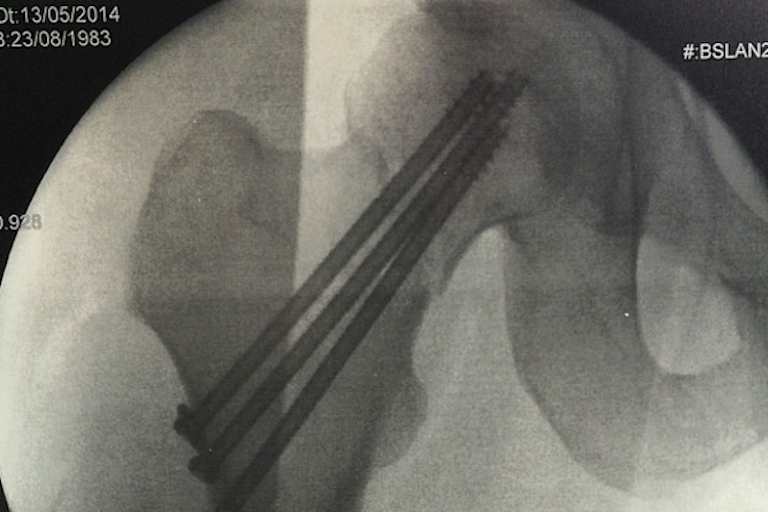

Eigentlich sollte Luca Scassa an diesem Wochenende Danilo Petrucci auf die ART von IodaRacing ersetzen, nach seinem Sturz beim Mugello-Test vor fünf Tagen wird der Superbike-Pilot länger pausieren müssen als sein Landsmann. Scassa flog in der zweiten Kurve (sie trägt den passenden Namen 'Luco') mit einem mächtigen Highsider von seinem Bike und landete hart auf der rechten Seite: Oberschenkelhalsbruch!

Noch am selben Tag wurde der 30-Jährige operiert, mit drei Schrauben wurde der Knochen fixiert. Nun steht Scassa ein langer Genesungsweg bevor, die Ärzte verordneten ihm drei Wochen Bettruhe. "Ich fühle mich buchstäblich wie durch den Wolf gedreht", stöhnte Scacca aus dem Krankenbett. "Wegen der Schmerzen konnte ich kaum schlafen. Ich muss jetzt drei Wochen liegen." Scassa wird somit acht Wochen ausfallen, die Meetings in Donington, Sepang und auch sein Heimrennen in Misano wird er in jedem Fall verpassen. "Ich hoffe in Portimao oder Laguna Seca wieder zurückzukommen", sagt Scassa zerknirscht.